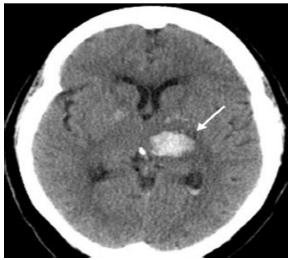

Paciente de 25 anos, do sexo feminino, usuária de anticoncepcional oral combinado, obesa, tabagista, sem outras comorbidades.

Internada na UTI com relato de cefaleia progressiva, em peso, com piora nas últimas 24h, agora bastante intensa e associada a náuseas e a vômitos.

Diante desse caso, foi realizada a tomografia de crânio que gerou a imagem a seguir.

A conduta adequada para essa doente é o(a)